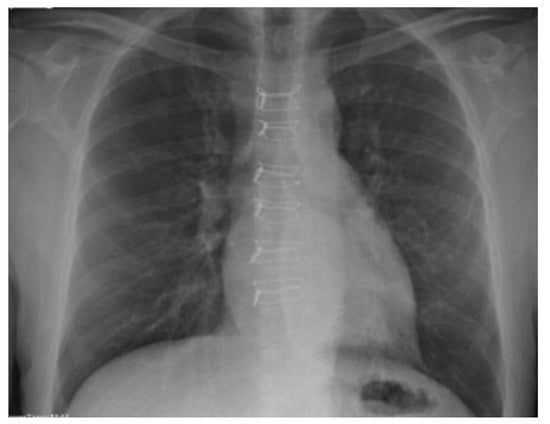

- Jolly, S.; Flom, B.; Dyke, C. Cabled Butterfly Closure: A Novel Technique for Sternal Closure. Ann. Thorac. Surg. 2012, 94, 1359–1361. [Google Scholar] [CrossRef] [PubMed]

- Antonič, M.; Petrovič, R.; Miksić, N.G. Thermoactive Nitinol Clips as Primary and Secondary Sternal Closure after Cardiac Surgery—First Experience in Slovenia. Acta Clin. Croat. 2021, 60, 435–440. [Google Scholar] [CrossRef] [PubMed]

- Stelly, M.M.; Rodning, C.B.; Stelly, T.C. Reduction in deep sternal wound infection with use of a peristernal cable-tie closure system: A retrospective case series. J. Cardiothorac. Surg. 2015, 10, 166. [Google Scholar] [CrossRef] [PubMed][Green Version]